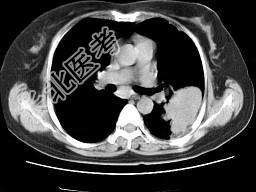

- 单项选择题女,52岁, 左侧背痛一月,胸部CT如图, 最可能的诊断为 ( )

A、左肺中央型肺癌

B、左肺周围型肺癌

C、左肺感染

D、左肺炎性假瘤

E、肺隔离征